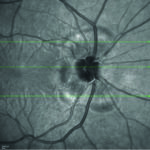

Una cefalea da indagare: diagnosi di sindrome di Vogt Koyanagi Harada